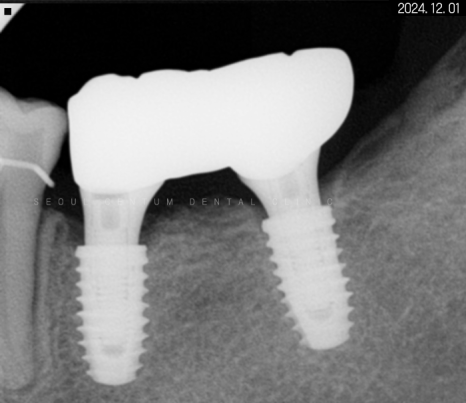

일정 기간이 지난 후 고정력을 체크하고

지대주에 이어서

크라운까지 예쁘게 수복해 드렸습니다~

크라운으로 감싸고 난 후의 치근단 모습입니다.

정확한 간격으로 견고하게 심어졌으며

주변 치조골 양도 풍부합니다.